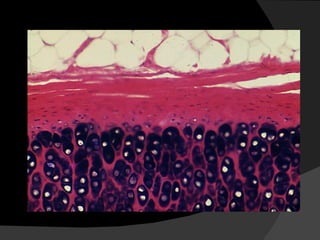

Cartílago Está formado por una abundante matriz extracelular en la cuál los condrocitos se ubican en espacios llamados lagunas

Cartílago Los condrocitos sintetizan y secretan los componentes orgánicos de la matriz extracelular que son básicamente colágeno, ácido hialurónico. proteoglicanos y glicoproteínas, y según las características de la matriz se distingue cartílago hialino y fibroso.

Cartílago Existe además el cartilago elástico en el cuál la elastina forma parte de la matriz extracelular. Los vasos sanguíneos no penetran a la matriz cartilaginosa y los condrocitos se nutren con material que difunde desde de los capilares sanguíneos del tejido conjuntivo adyacente.

Cartílago Cada placa o lámina de tejido cartilaginoso está rodeada por el pericondrio que corresponde a tejido conjuntivo denso en el cuál se distingue una capa externa fibrosa y una capa interna celular en la cual se ubican las células que pueden dar origen a los condroblastos,

que corresponden a precursores de los condrocitos y que difieren de ellos solo en su edad y en su mayor actividad de la sintesis de componentes de la matriz intercelular cartilaginosa.